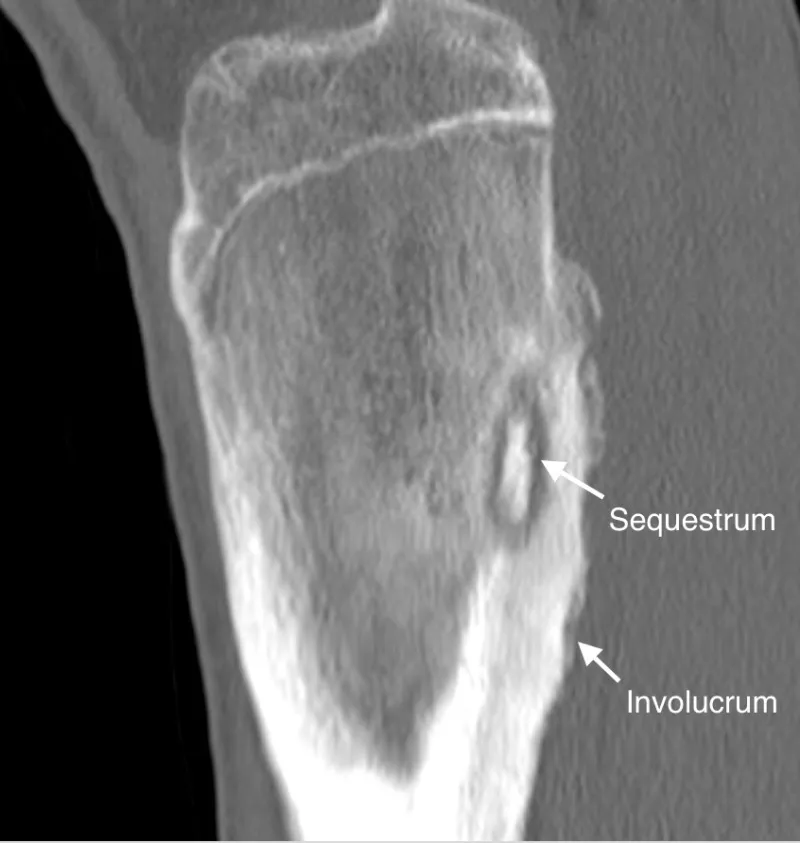

- Sequestrum: Necrotic bone.

- Involucrum: New periosteal bone.

- → Ischemic necrosis → Sequestrum (avascular bone fragment).

- → Periosteal reaction → Involucrum (new bone surrounding sequestrum). 📌 Sequestrum (dead) 'sequestered' by Involucrum (new).

- CT: Details cortical destruction, sequestra.

⭐ Sequestrum (dead bone) and Involucrum (new bone formation around sequestrum) are hallmark radiological signs of chronic osteomyelitis.

- Sequestrum (dead bone) & involucrum (new bone) are hallmarks of chronic osteomyelitis.